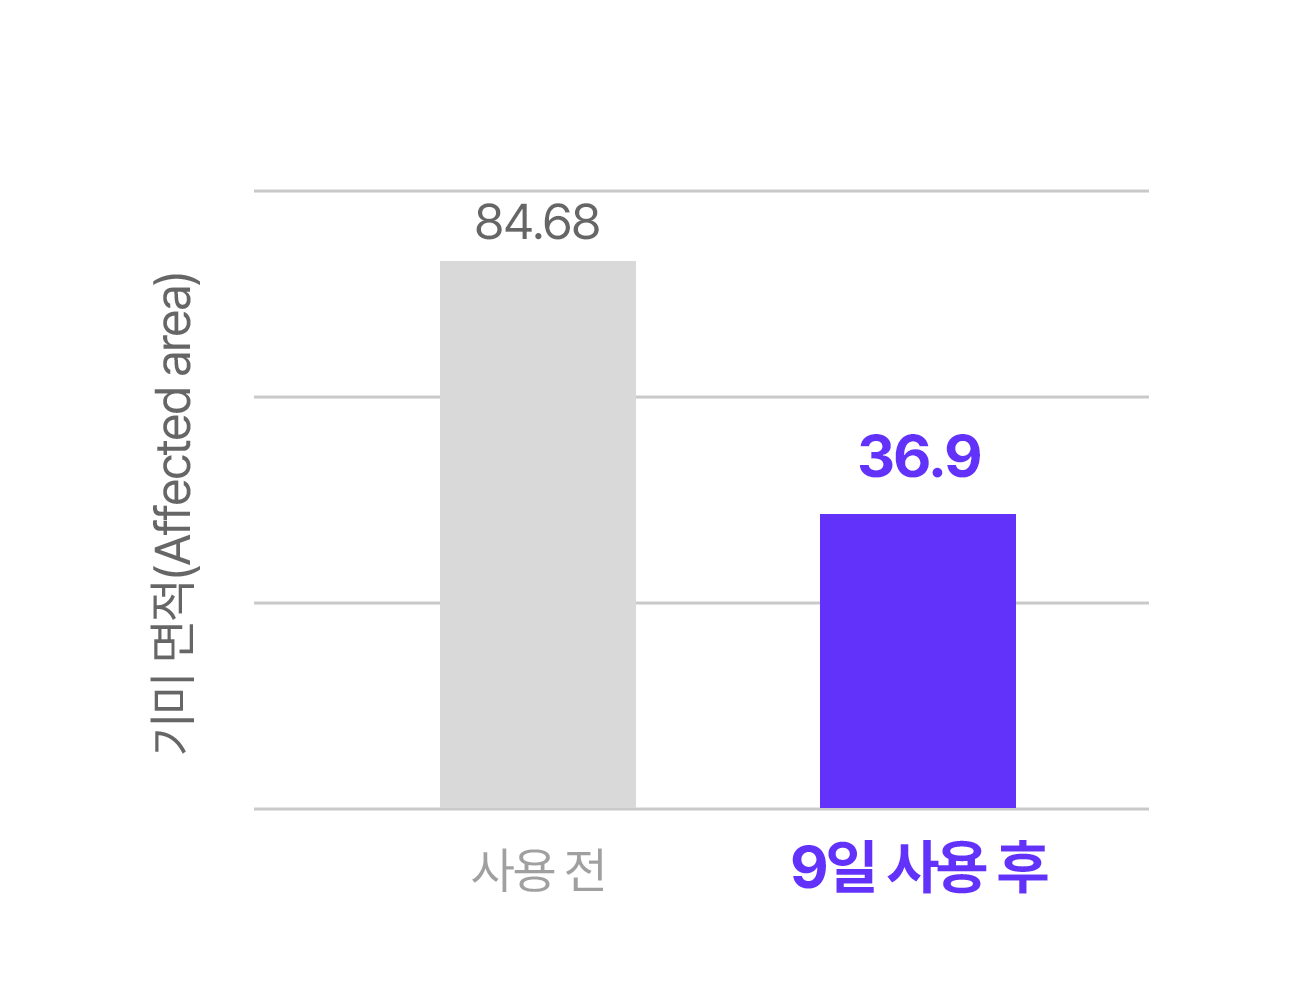

Q1. 정말 9일만에 효과를 느낄 수 있나요?

A. 실제 임상 실험과 소비자 테스트 결과, 피부톤 개선과 잡티 완화에 있어 9일 안에 변화를 체감한 사용자가 많았습니다. 물론 개인 피부 상태에 따라 차이는 있을 수 있으나, 빠른 효과를 목표로 설계된 제품입니다.